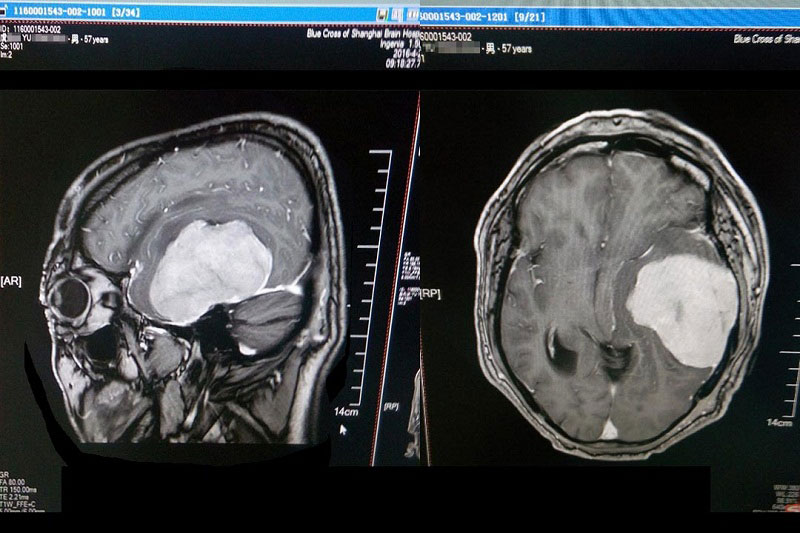

术前检查肿瘤清晰可见

患者入院后行头颅MR+增强及MRA发现:肿瘤供血丰富,供血起源于小脑幕上动脉。经包括沈建康教授在内的专家会诊后,考虑到患者脑肿瘤巨大(8*6cm)、肿瘤周边血供丰富,手术指征明确,常规手术切除恐出血过多,增加手术风险,决定术前先为虞文军行“超选择性全脑血管造影术+脑膜瘤供血动脉栓塞术”,对肿瘤供血动脉进行栓塞,减少出血量,再全麻下行“左侧颞底部巨大脑膜瘤切除术”。 沈建康教授表示:“ 我10年都没见过这么大的脑肿瘤了”。 患者术后随即恢复清醒,自我感觉头脑较前更清醒,语音、语速恢复较好,不到半个月便已能正常行走,顺利出院。